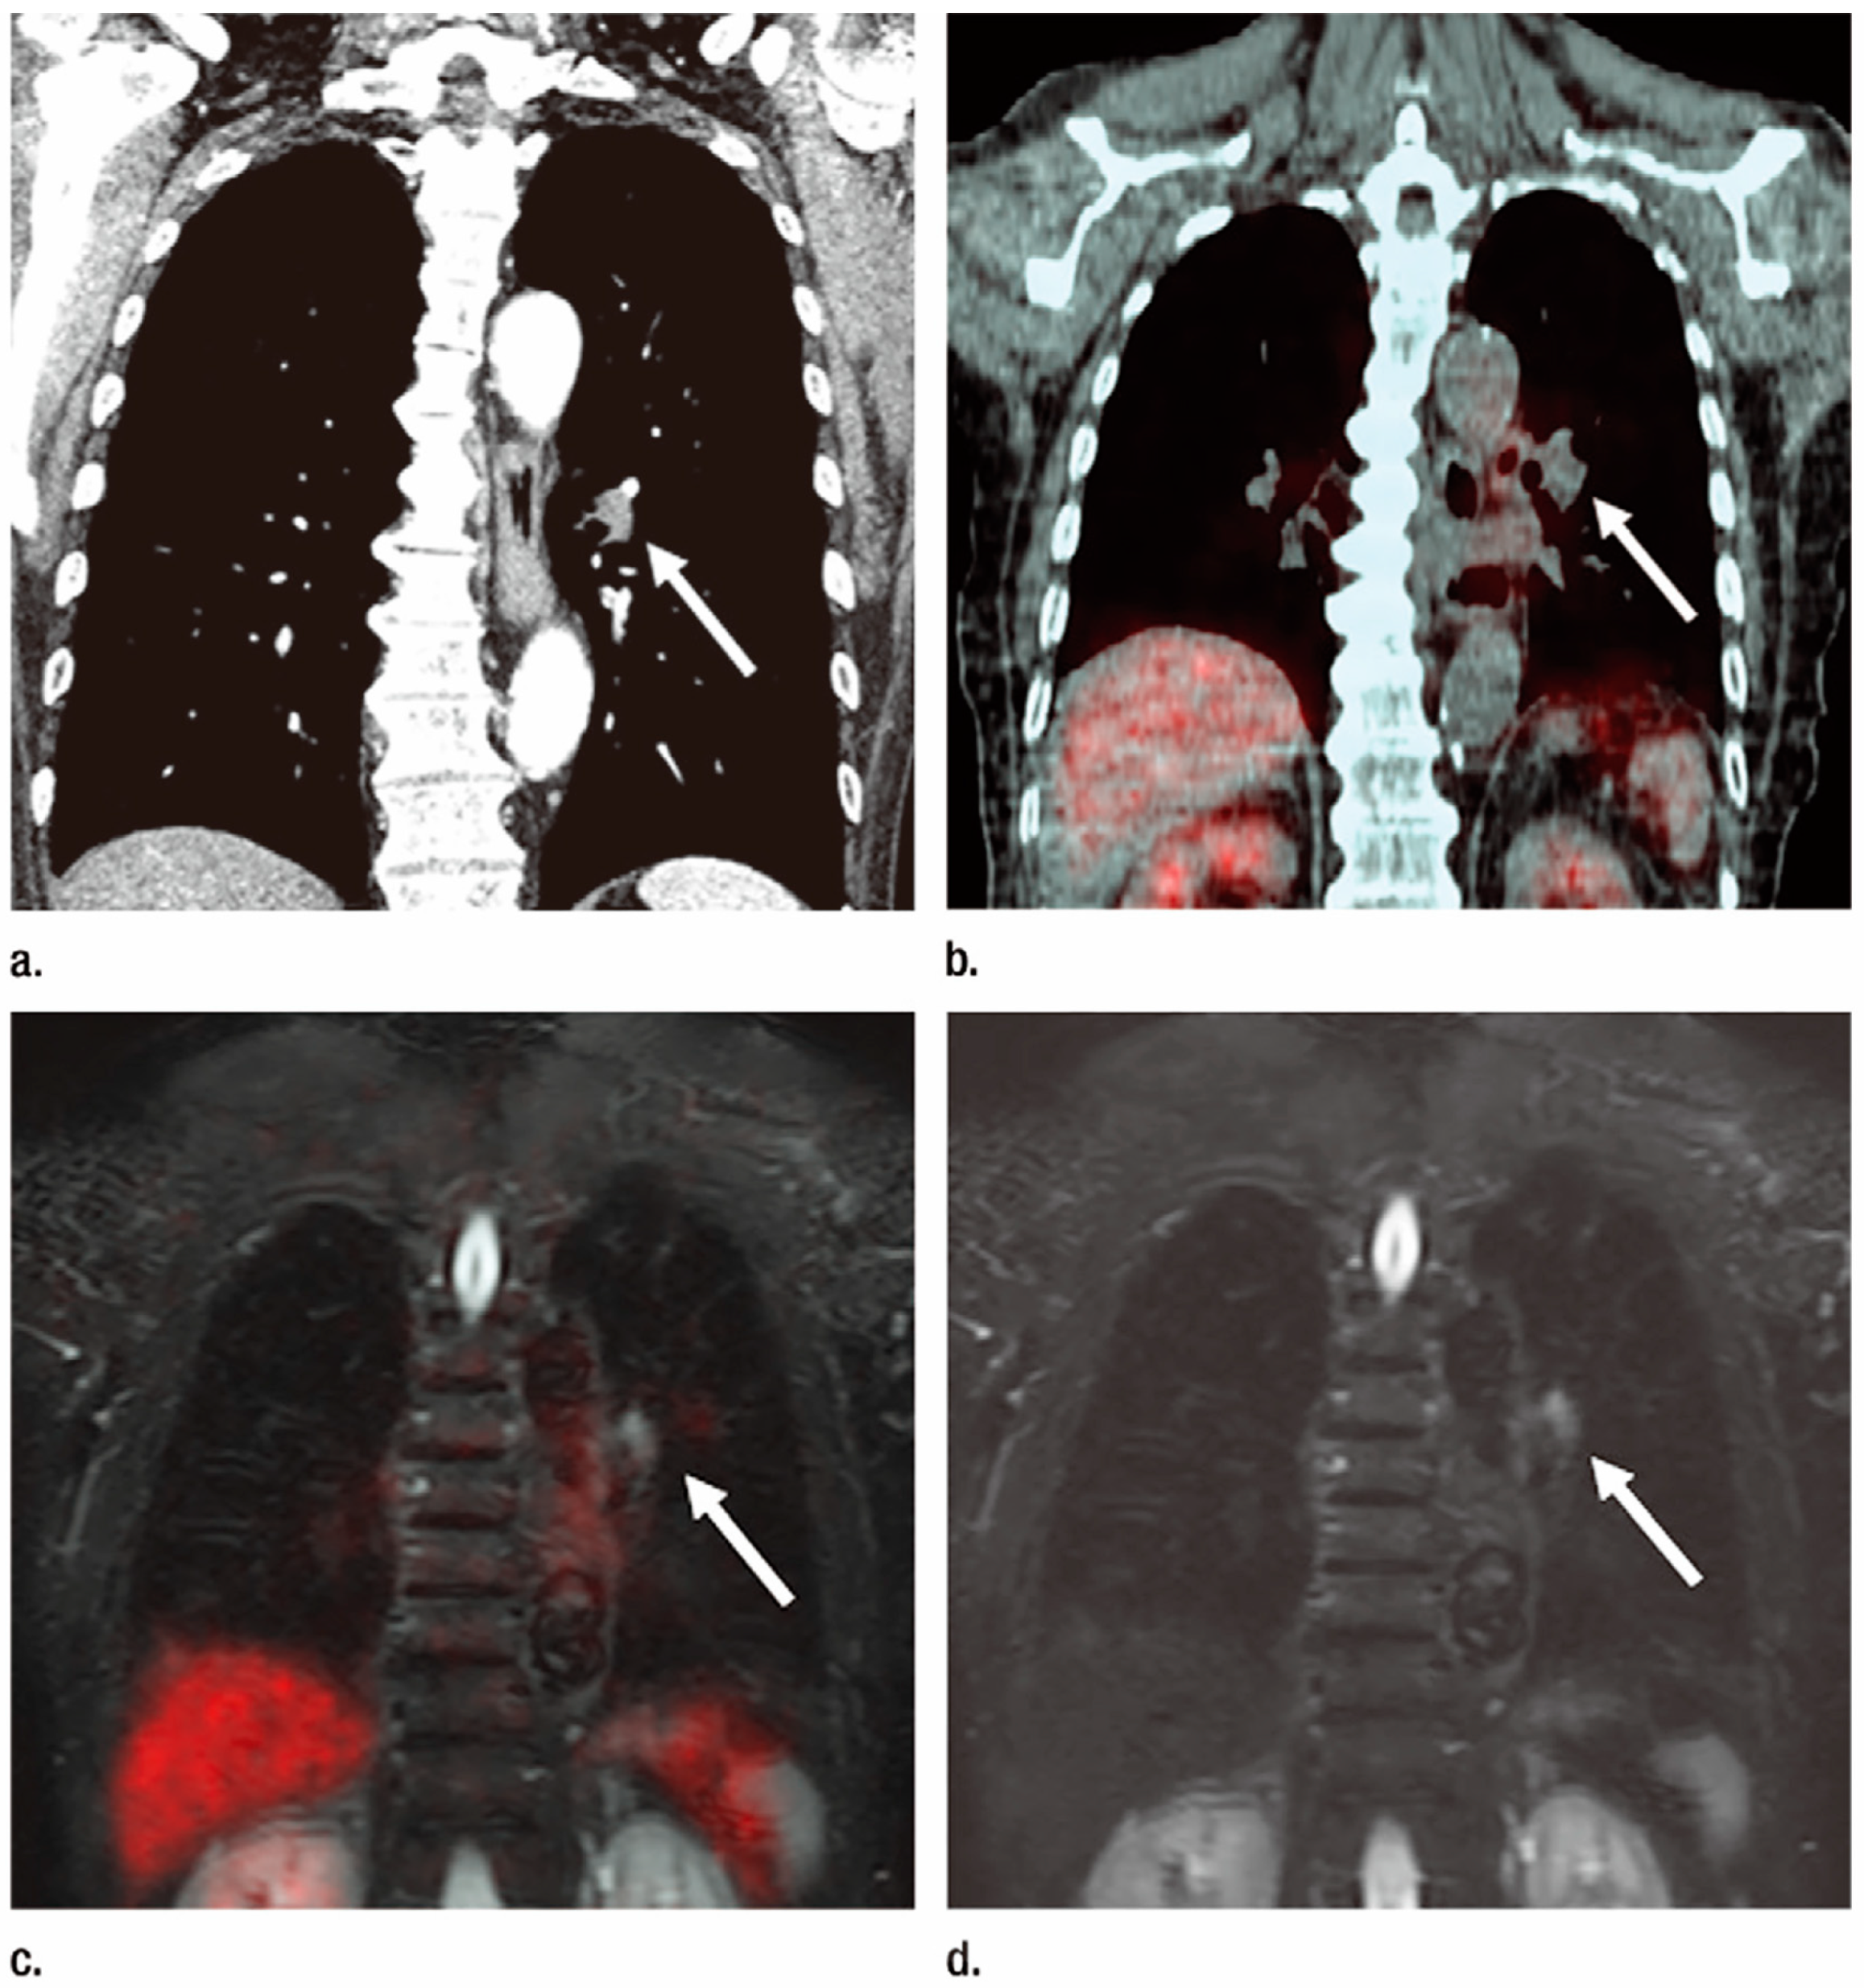

3.2. N-Factor Assessment